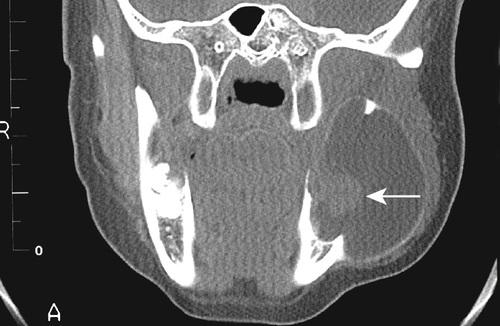

Computed tomography (CT) scan showing a large cyst involving the crown of an unerupted maxillary third molar.

odontogenic keratocyst (OKC)